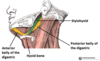

What is this muscle?

What is this muscle?